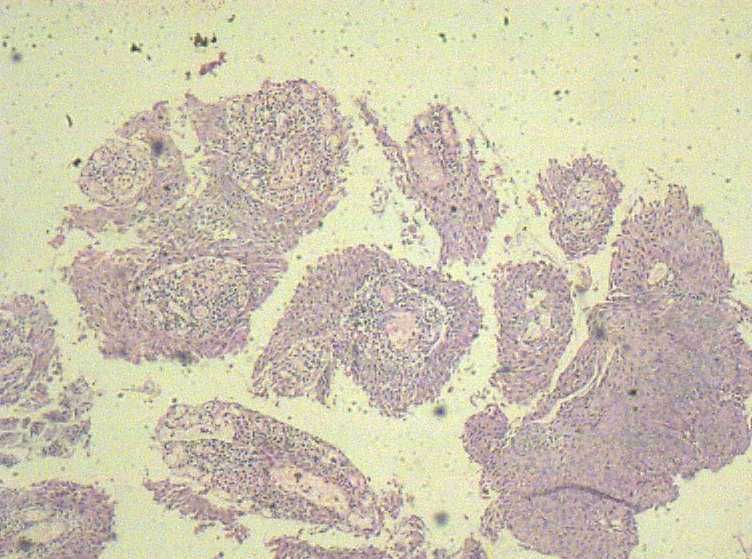

33岁 宫颈刮片看上去很像腺上皮病变,报了AGC 建议活检。 活检取自宫颈,图片如下:请帮忙看下,谢谢!

鳞状上皮增厚,乳头状增生,并见挖空样细胞。提示HPV感染。

鳞状上皮乳头瘤样增生,建议HPV检测

尖锐湿疣

有不典型增生, 不知道大家有没有看到。  如果有不典型和上面的图像可或直接报 :尖锐湿疣伴不典型增生。